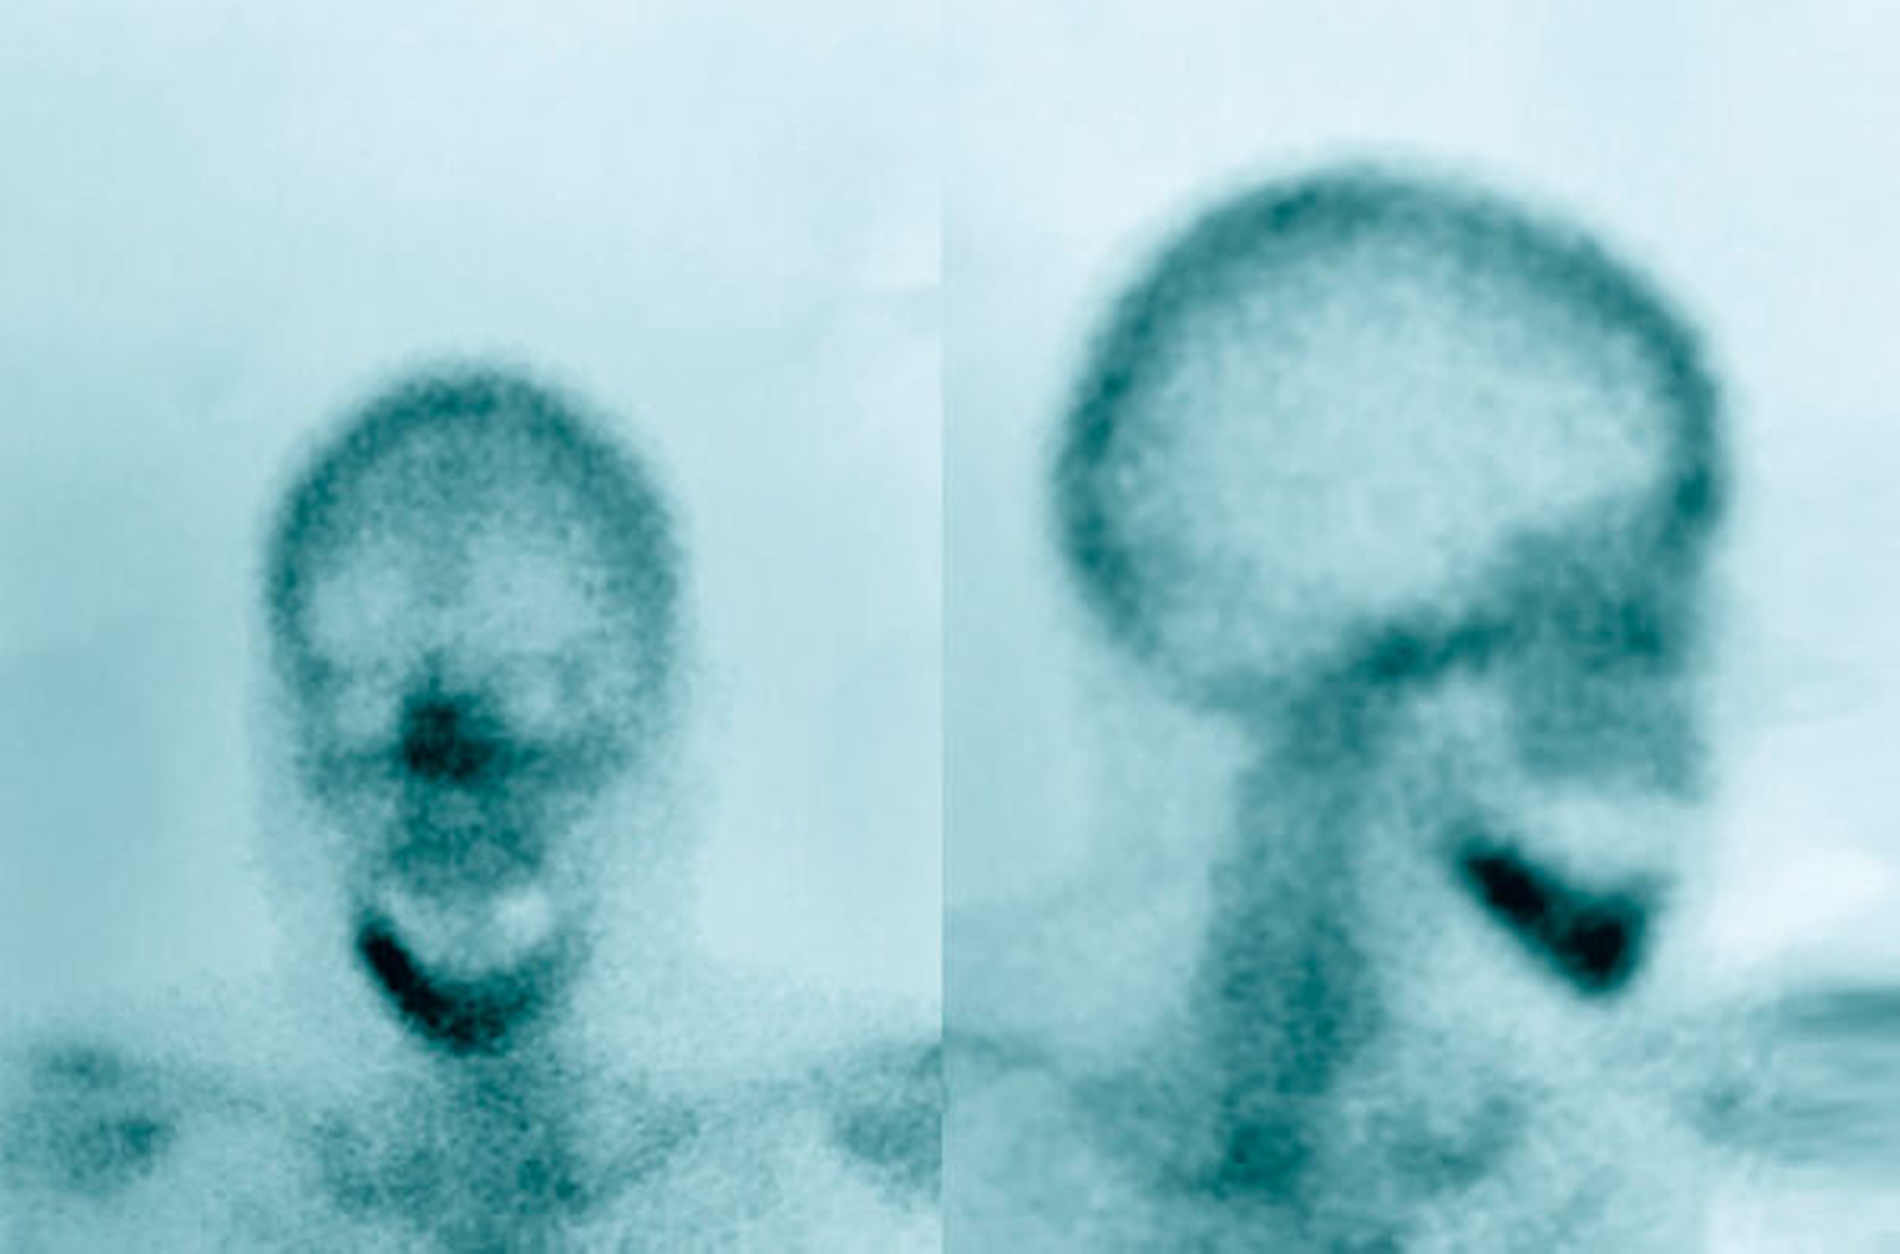

In radiologischen Untersuchungen zeigt sich bei konventionellen Röntgenaufnahmen und in der CT-Bildgebung im betroffenen Kieferareal eine vermehrte Sklerosierung des Knochens ohne Sequesterbildung (Abbildungen 1 bis 3). In der Szintigrafie des Unterkiefers zeigt sich ein chronisch entzündlicher Prozess ohne Anzeichen für eine floride bakterielle Entzündung [van Merkesteyn et al., 1988] (Abbildung 3).